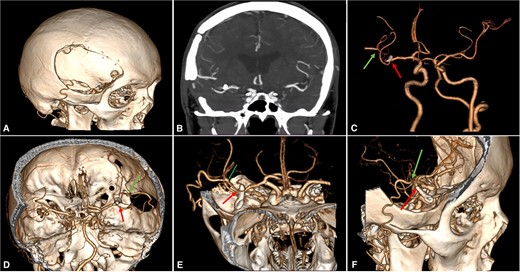

Postoperative brain imaging showed adequate bypass patency with aneurysm exclusion from the circulation (Video S1 and Fig. 3). The patient was discharged 13 days later with a GCS score of 15 and a modified Rankin Score (mRS) of 1. At the 6-month follow-up, the patient was neurologically intact (mRS: 0).

Postoperative Imaging. (A) 3-Dimensional image reconstruction shows the craniotomy with the entrance of the STA into the skull; (B) Coronal view of a maximum intensity projected multislice spiral CT shows the permanent clip placed with the exclusion of the fusiform aneurysm; (C)–(F) Cranial views depict patency of the STA-MCA bypass (green arrow) and clipping of the M2 proximal segment (red arrow). CT: computed tomography, MCA: middle cerebral artery, STA: superficial temporal artery.